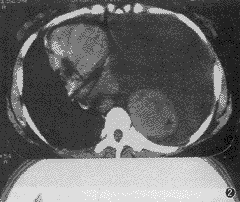

第32例——左胸大片片状阴影一例

患者女性 ......